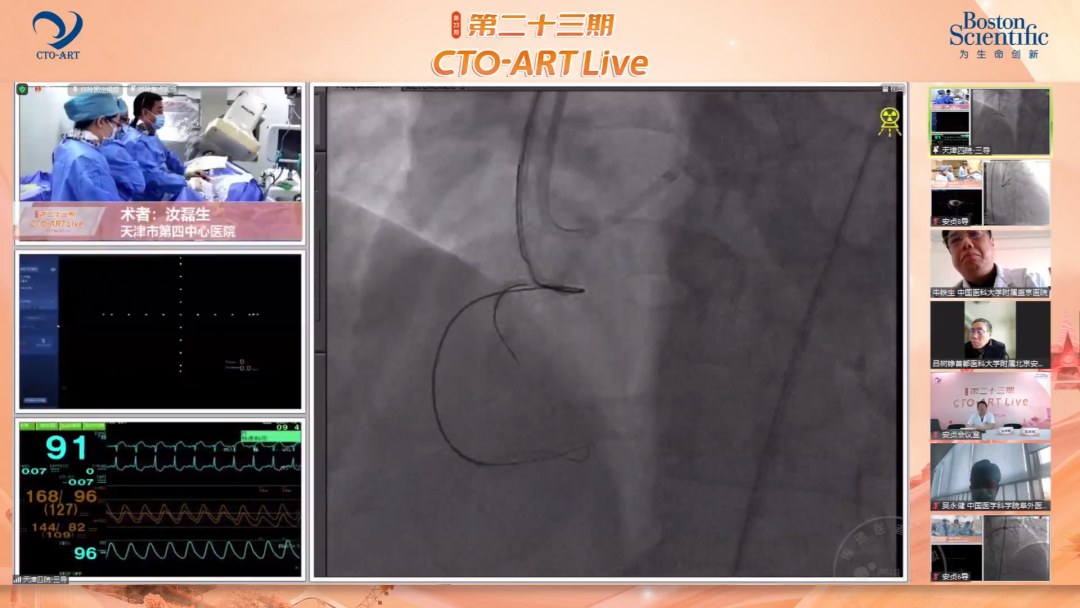

首都医科大学附属北京安贞医院吴铮教授演示了本次会议的第一例CTO手术转播,这是一例既往开通失败的高难度右冠CTO,后续由首都医科大学附属北京安贞医院李宇教授、彭红玉教授、祖晓麟教授、高海教授、赵林教授、赵东晖教授、聂绍平教授、阙斌教授、宋现涛教授和张闽教授团队,四川大学华西医院贺勇教授、张立教授、李晨教授、王华教授、周名纲教授、王勉教授和陈勇教授团队,以及天津市第四中心医院温尚煜教授白求恩国际和平医院汝磊生教授相继上线演示了多例精彩的CTO PCI手术,涉及各种高难度手术操作技巧。

来自全国各地众多知名CTO PCI术者作为讨论嘉宾纷纷现身云端,在线参与讨论和点评。在手术演示环节与介入术者一道,面对复杂病例时集思广益,实时为术者出谋划策。专家们在复盘环节表示,策略的灵活转换对于提高CTO PCI的手术成功率非常重要,同时也对术者的手术技术水平提出了更高的要求。专家们还强调,若患者存在逆向开通的条件,那么在起初尝试正向策略时应该如何把握启动逆向策略的时机也是术者需要深入思考的问题之一,正向的导丝尝试到何种程度时可以开始逆向准备是CTO PCI实战中的关键。